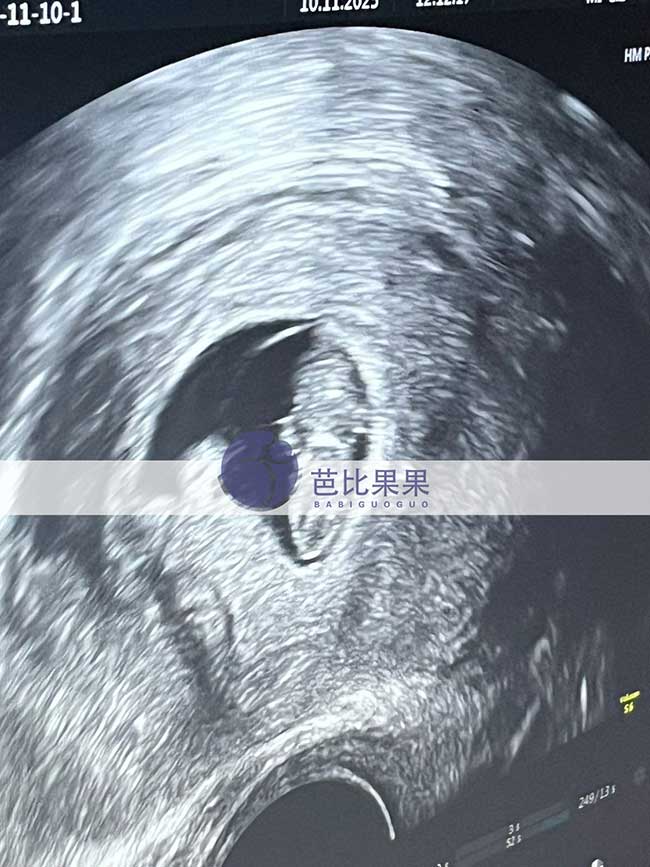

苏先生在格鲁吉亚匹配的试管妈妈来医院做B超啦,胎宝宝发育的很好,试管状态也棒棒的

苏先生在格鲁吉亚匹配的试管妈妈来医院做B超

秦先生到格鲁吉亚匹配的试管妈妈来医院做首次B超